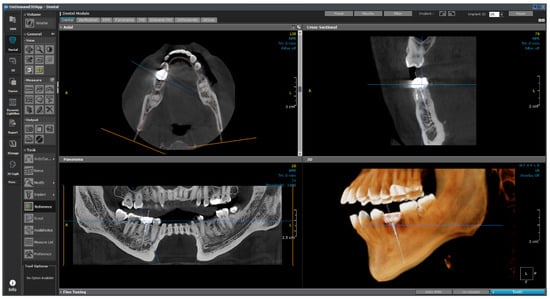

The software consists of modules such as demineralized bone matrix, Dental, 3D, 3D Cephalometric, Fusion, Dynamic LightBox, Report, Xlmage, and In2Guide, and each module functions independently. The dental module applied in this study is the standard for 3D dental reconstruction. This module contains eight different layouts, including dental, verification, multiplanar reformation (MPR), panorama, temporomandibular joint (TMJ), bilateral-TMJ, orthodontic, and airway. As shown in Figure 24, implant surgery can now be fully simulated using the dental module with the help of our real-size library of implant fixtures and abutments as well as the intra-oral/3D model scan data alignment function.

This module plays an auxiliary role for the user by integrating the implant ROM model to provide additional information. All necessary parameters from the implant ROM can be obtained from this module. As shown in Figure 25, the implant to be used is selected from the implant library by selecting the location of the tooth to be installed. Based on the selected location, appropriate bone material property values can be obtained, as shown in Figure 26.

Figure 26. Bone information.